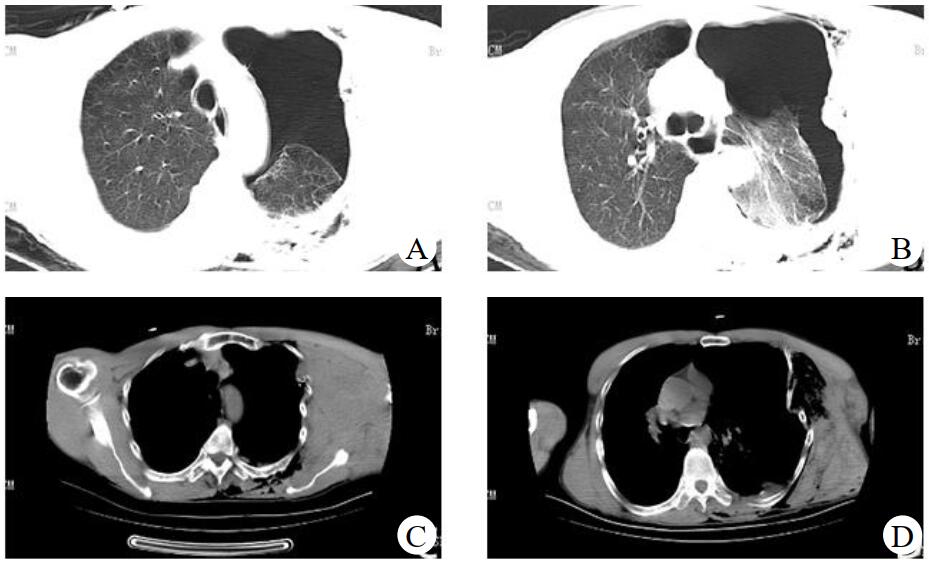

术后返回EICU,患者生命体征逐渐平稳,血管活性药物剂量逐步下调,复查CT及三维重建未见新发血肿,见图 3。1周后脱机拔管,10 d后拔除胸引管,2周后转出监护室。术后停用镇静镇痛药物后即发现患者存在腋神经、臂丛神经损伤迹象,后转至骨科行肌电图,提示臂丛神经上、中、下三支均严重受损,后期行康复治疗。

| 图 3 术后复查胸部CT及三维重建 |